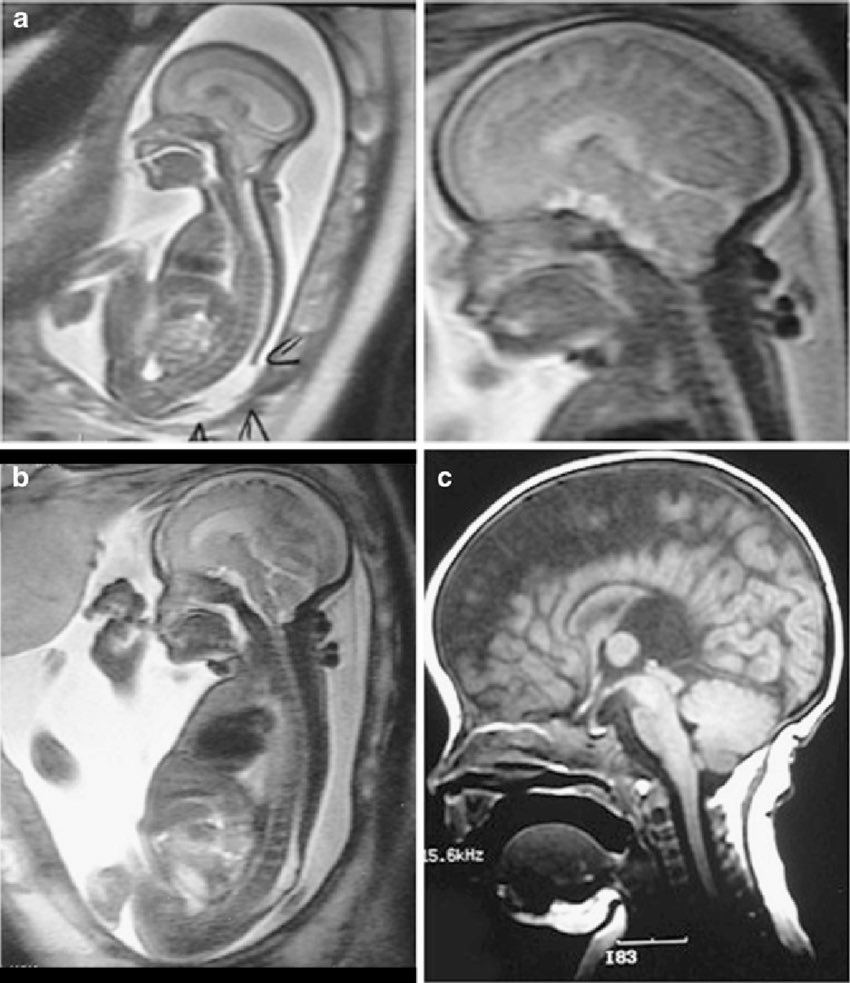

No existe riesgo demostrados de los exámenes por RM en las mujeres embarazadas o los bebés que aún no han nacido. No debe rechazar hacerse un examen por RM necesario para el diagnóstico de una enfermedad o de su bebe potencialmente grave o urgente porque le tenga miedo al examen.